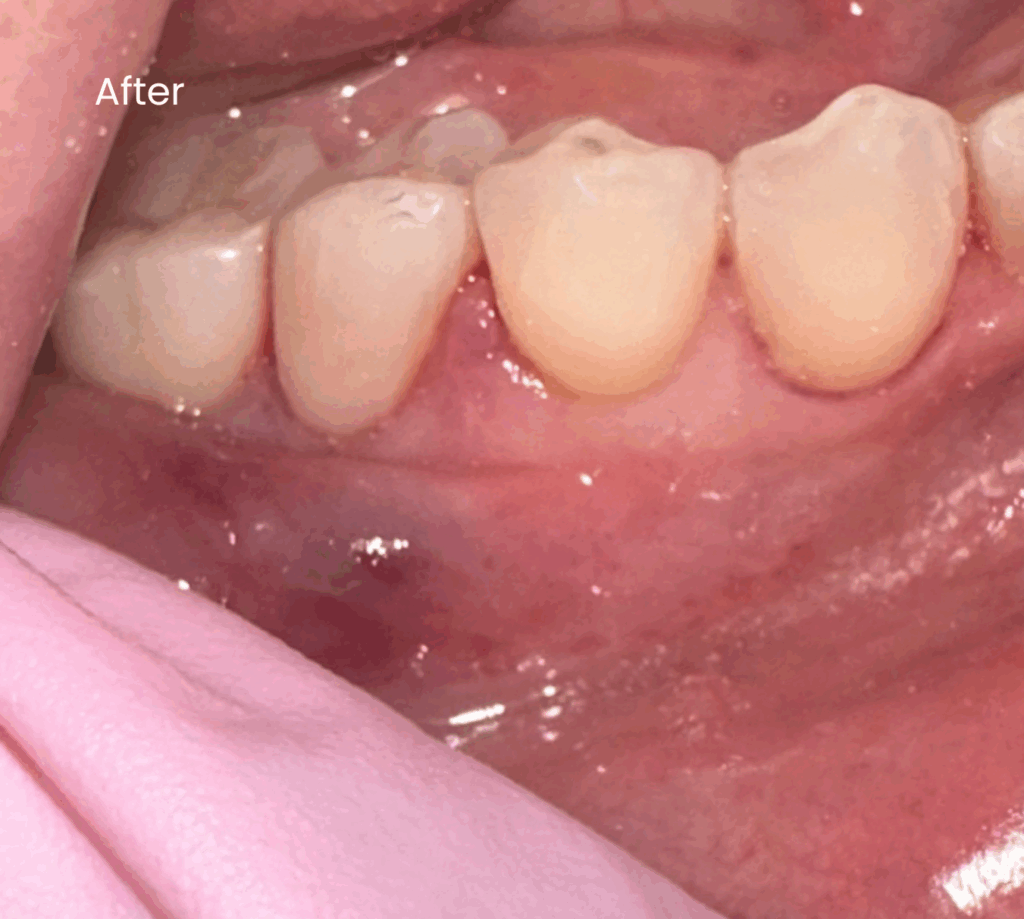

Before & After

Below are examples of the cosmetic outcomes that may be achieved with BPA-free gum coverings. Images are used with full patient consent. Individual results may vary.

After